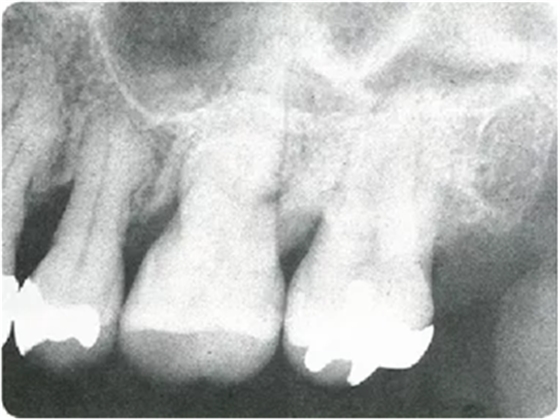

牙周探诊在掌握眼睛看不到的部分的状态方面,是非常重要的一个检查。参考X片进行探诊,可以立体掌握该检查部位。

然而X片中无法看到所有信息。鱼食,牙周探针的工作尖需要像步行一样在袋底走动运用步行式探诊法可以更准确掌握该部位的状况。

如果在对哪个部位进行到什么程度没有预想的状态下进行探诊,由于复杂的根面形态和牙周状态,无法正确插入探针、被牙结石挡住、遗漏等就很容易发生。

因此,在检测牙周袋深度时,通过 X 片确定牙槽骨的状态、根的形态、牙结石的附着状态等,在脑中有一个大致的印象,应该可以很大程度上减少漏检。

仅通过口腔视诊是无法看出何处有骨吸收的。通过拍摄的牙片,可以一定程度上掌握牙槽骨吸收的情况。

如果观察X片后预想的状态和牙周探诊分析出的状况有很大差异,就需要再次注意此部位并重新做一次牙周探诊。